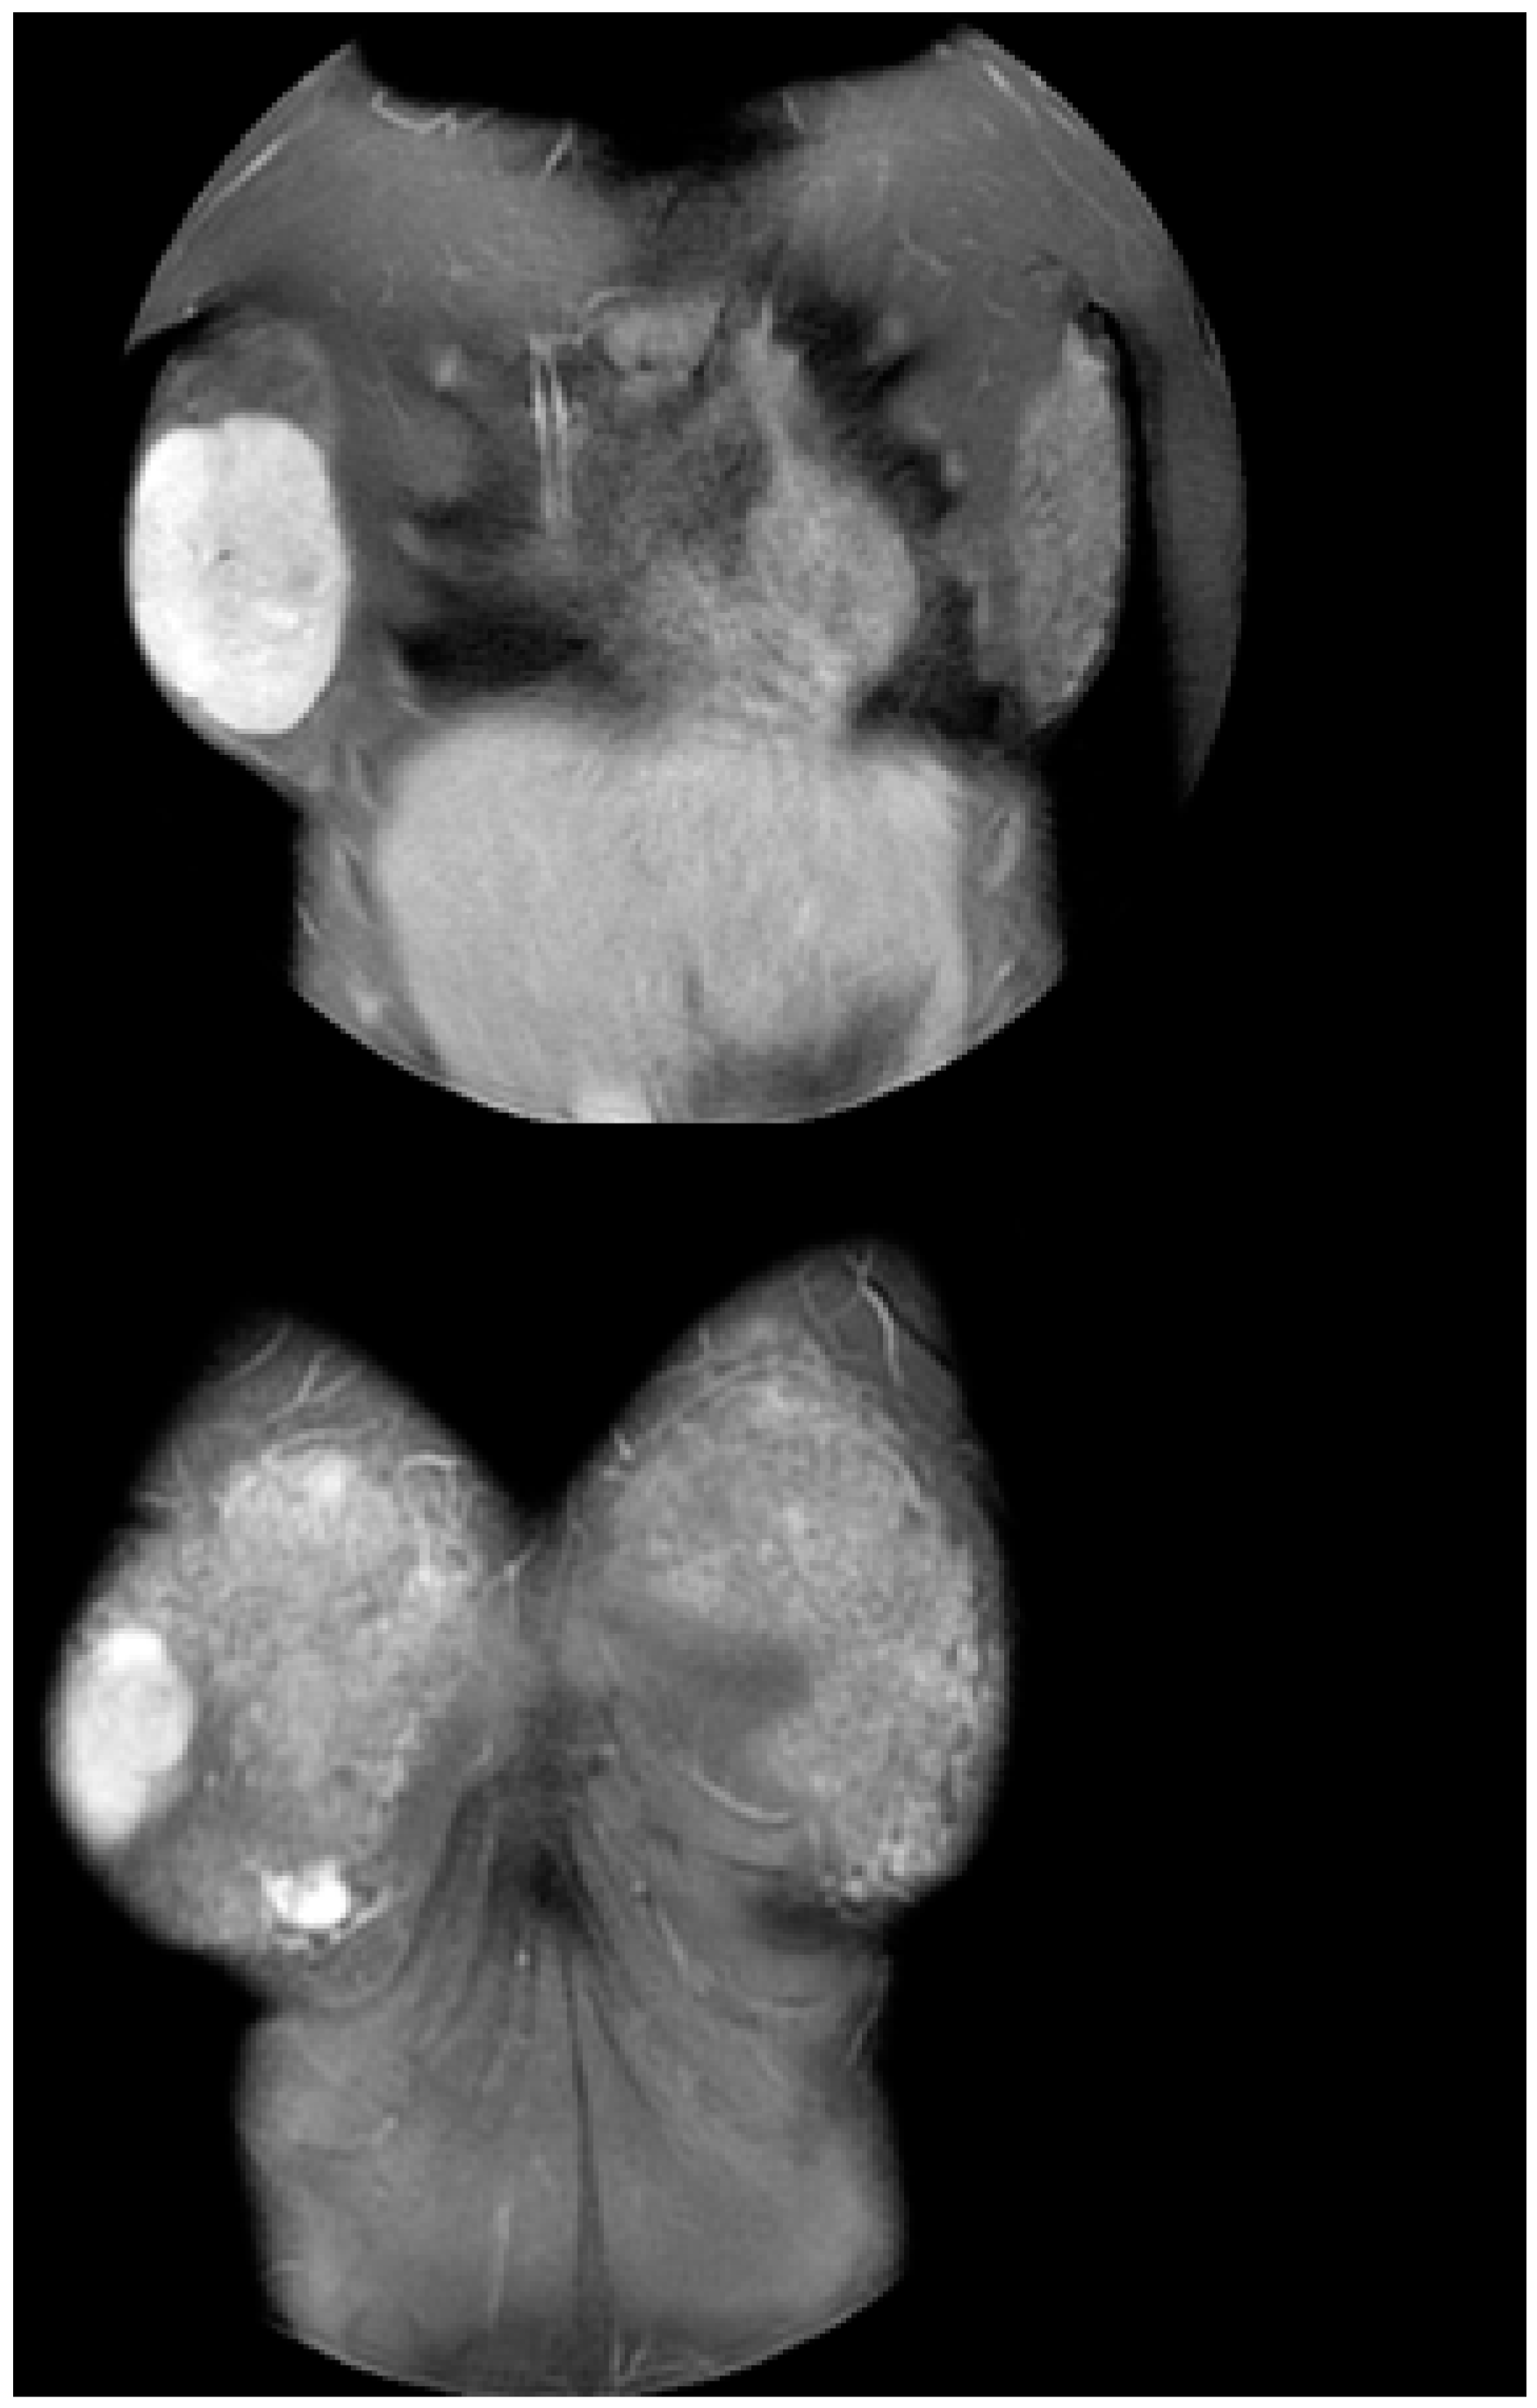

| Eleftheriades et al. 2022 (our case) | Greece | 10 × 8 × 2.5 | unilateral | right | 11 | pre | total lump excision | 1 |